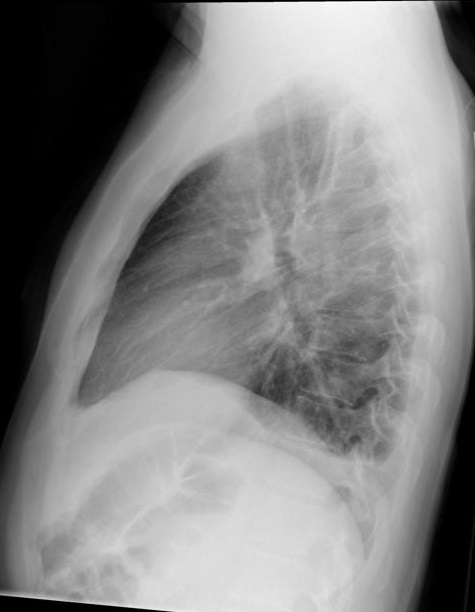

Image radiologique de

profile droit d'une epanchement liquidien pleurale

de faible abondance du poumon droit . La pleuresie

situe au sinus posterieure-lateral droit du poumon

droit . |